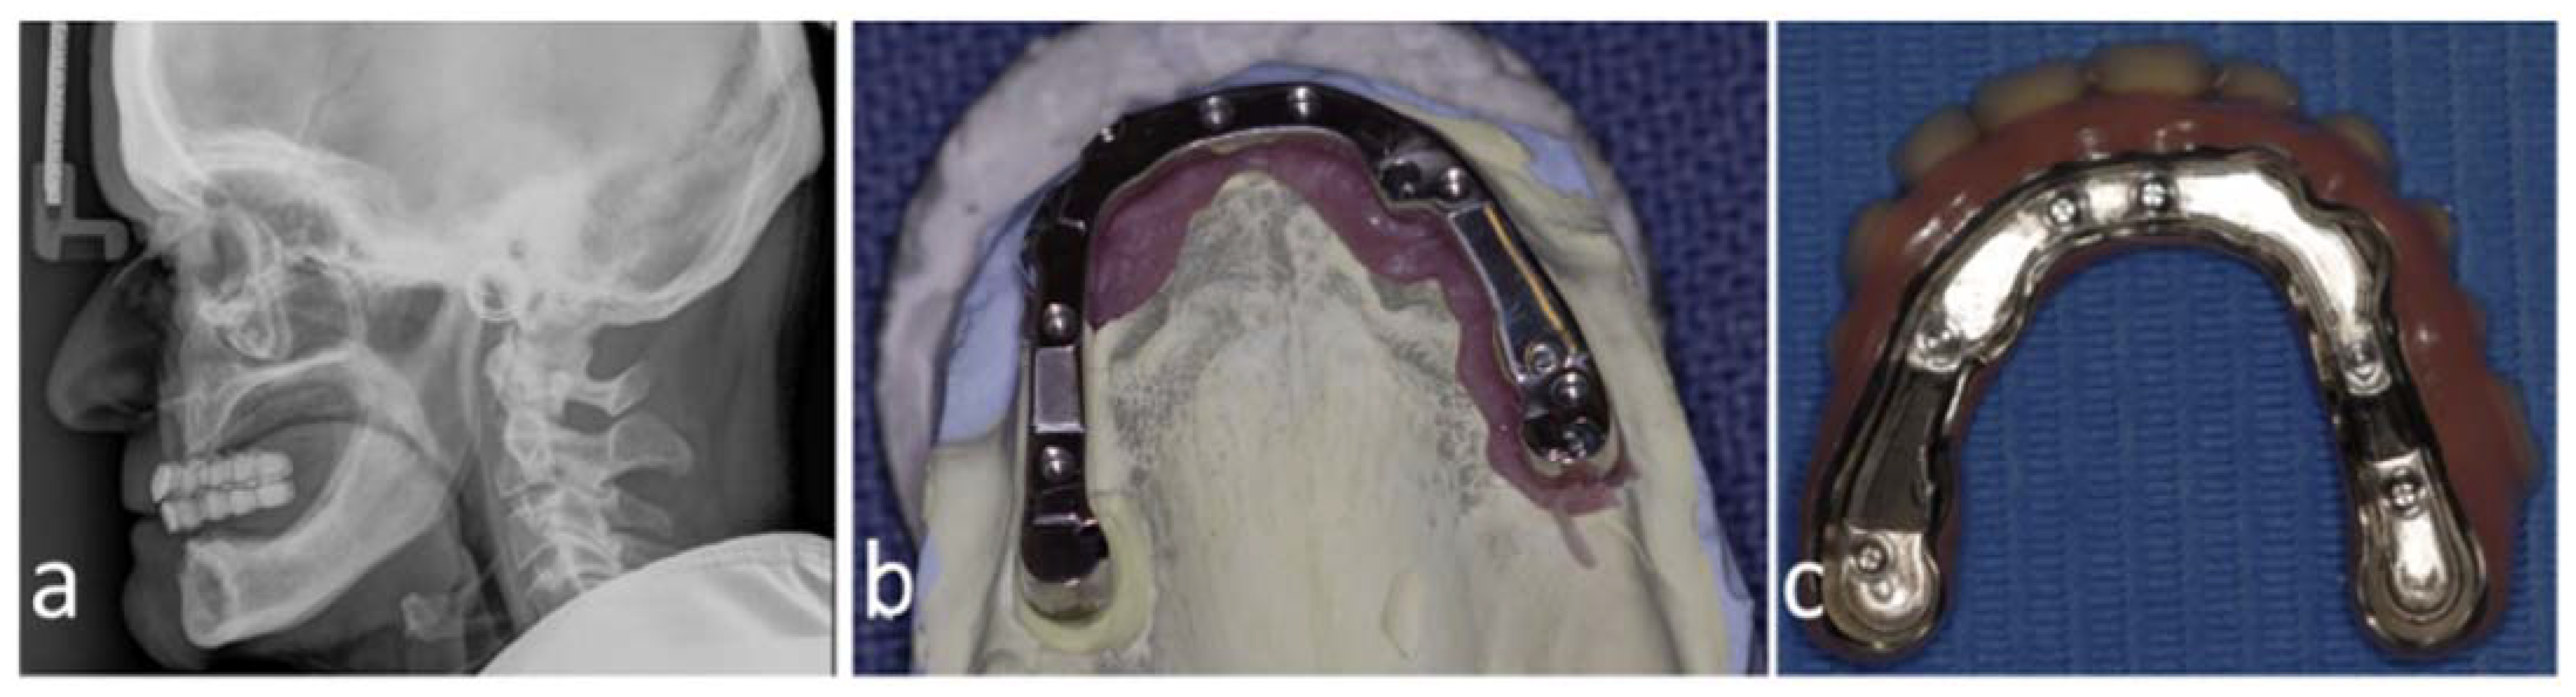

Figure 2.

Primary computed tomography (CT) of patient no. 6 upon arrival (a). Most of the maxilla and nasal structures are missing, the outer frame of the zygomatic bones have comminuted fracture, and the mandible has comminuted fracture as well as some missing parts. The bleeding was tamponated with cloth, and the radio-opague marking of the tissue can be seen in the 3D reconstruction. The missing bone in the maxilla and mandible of the patient no. 6 had been reconstructed earlier with vascularized bone using microvascular free flap positioned in the desired vertical and horizontal position using virtual planning and CAM-produced osteosynthesis (Planmeca Promodel, Helsinki, Finland). The custom osteosynthesis from the reconstructed maxilla had been mostly removed for dental reconstruction (upper b). The final dental rehabilitation involved a two-in-one structure in the maxilla and a conventional implant bridge in the mandible (lower b).